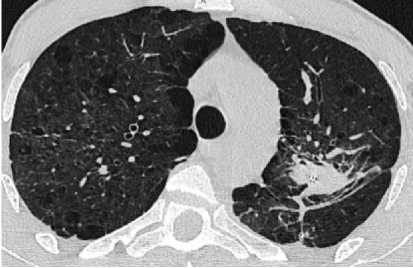

На контрольной КТ ОГК (25.07.2024) – апикальная плевра деформирована плевропульмональными спайками. «Свежих» очаговых изменений не выявлено. Левое лёгкое уменьшено в объёме из-за хирургического лечения. В прикорневой зоне на фоне утолщённого междолькового интерстиция прослеживаются цепочки металлических швов в локальном участке уплотнения со сближенными и деформированными просветами бронхов, с локальным утолщением костальной и междолевой плевры с незначительным количеством плеврального выпота пара-костально. В апикальном отделе S1 правого лёгкого сохраняется субплевральный участок консолидации с видимыми просветами бронхов в структуре (рис. 5).

а

Рисунок 5. Аксиальные срезы КТ органов грудной клетки, лёгочное окно: а – левое лёгкое уменьшено в объёме из-за хирургического лечения. В прикорневой зоне на фоне утолщенного междолькового интерстиция прослеживаются цепочки металлических швов; б – на фоне выраженных фиброзных и буллезно-дистрофических изменений визуализируются множественные мелкие очаги вдоль междолевой плевры обоих лёгких

Figure 5. Axial CT scans of the chest organs, pulmonary window: a – the left lung is reduced in volume due to surgical treatment. In the basal zone, chains of metal sutures are traced against the background of a thickened interlobular interstitium; b – against the background of pronounced fibrous and bullous-dystrophic changes, multiple small foci are visualized along the interlobular pleura of both lungs

б